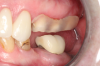

Fig 13. Lateral view after placement.

Figure 13

Fig 18. Preoperative image.

Figure 18

Fig 19. Atraumatic extraction.

Figure 19

Occasionally dentists are presented with extreme challenges with long-term restorations and replacing missing teeth. Dentists must evaluate the patient's condition, develop optimum long-term oral health, and attempt to meet the patient's expectations. Figure 18 showed a class III malocclusion with deep bite, multiple abfractions, and less-than-ideal occlusal plane, but the patient wanted to replace his maxillary right canine only. A discussion with the patient regarding occlusal disharmonies and comprehensive recommendations for full-mouth rehabilitation revealed that the patient had a limited budget for dental care. The patient understood the ramifications of his comprehensive dental needs not being affordable. Decisions were made to atraumatically remove the maxillary right canine (Figure 19) and immediately place a ceramic dental implant (Figure 20). Polytetrafluoroethylene (PTFE) 4-0 sutures were placed to help support soft tissues, and then a full-arch Essix-style retainer with a flowable composite facial veneer was used to provide some esthetics during the patient's healing phase (Figure 21). The implant and the retainer were not to be in contactthe retainer may occlude with the opposing dentition and also be passive in relation to the ceramic implant.